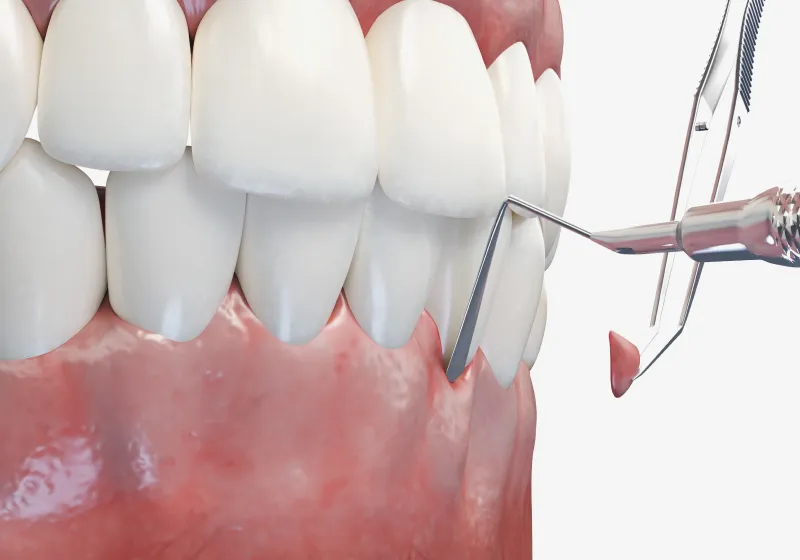

02原因を徹底的に除去

原因除去療法には患者さまが行うものと医療者サイドが行うものが あります。まず、患者さまは、ブラッシング技術を向上させ、それを習慣化することが大切です。そして医療者サイドが行う原因除去療法とは、患者さまが歯を磨きやすい状態に整えることです。そのためには“被せる”、“詰める”などの精度を高めること。より天然歯に近い形体を実現することにより、磨きやすい状態が整えられます。また、治療により歯周ポケットをなくしたり、歯磨きに負けない強い歯肉をつくることも大切です。

03マイクロスコープを用いた

精密な治療マイクロスコープという歯科用顕微鏡を用いて精密な治療を行うことが可能です。マイクロスコープを利用すると手元が20倍〜に拡大され肉眼では判断できない削るべき箇所、残すべき箇所を正確に判断可能です。

さらに、歯石は歯ブラシでは除去できず、歯科医院で専用の器具を使ったスケーリング(歯石除去)が必要になります。

歯周ポケット検査

まず行うのが「歯周ポケット検査」です。

専用の細い器具で、歯と歯ぐきの間にあるすき間(歯周ポケット)の深さを測定し、歯ぐきの健康状態を数値で確認します。

健康な歯ぐきのポケットは2~3mm程度ですが、4mmを超えると炎症が進行している可能性が高く、6mm以上になると中等度~重度の歯周病と診断されることもあります。 -

軽度の歯肉炎や初期の歯周炎であれば、まずは原因であるプラーク(歯垢)や歯石を取り除く「スケーリング」と、歯根の表面を滑らかに整える「SRP(ルートプレーニング)」が中心です。

専用の器具を使って歯ぐきの奥まで清掃し、細菌が再び付着しにくい状態に整えます。 -

中等度以上の歯肉炎

しかし、炎症が中等度以上に進行している場合には、歯ぐきの奥深くまで歯石や感染組織が入り込み、通常のクリーニングだけでは改善が難しくなります。

その場合は「歯周外科治療」を行い、歯ぐきを一部開いて直接歯根を露出させ、炎症の原因をしっかりと除去します。

これにより、深くなった歯周ポケットをリセットし、再感染を防ぐことができます。 -

フラップ手術

(歯肉剥離掻爬術)また、炎症が歯ぐきの深部まで進行している場合は、「フラップ手術(歯肉剥離掻爬術)」を実施します。

歯ぐきを丁寧に開いて奥深くの歯石や感染組織を直接確認しながら取り除く方法で、マイクロスコープを併用することで精密かつ低侵襲な処置が可能です。

これにより、術後の腫れや痛みを抑え、治癒を早める効果も期待できます。 -